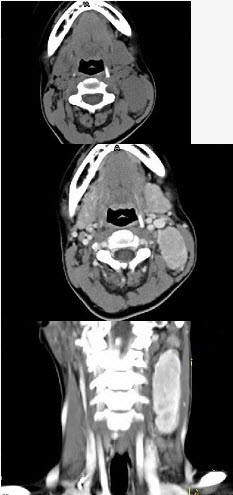

女,19岁,发现左颈部无痛性肿块2年余,可活动,CT如图所示,最可能诊断为()。

A、淋巴结炎

B、淋巴瘤

C、转移癌

D、淋巴结结核

E、巨淋巴结增生症

E